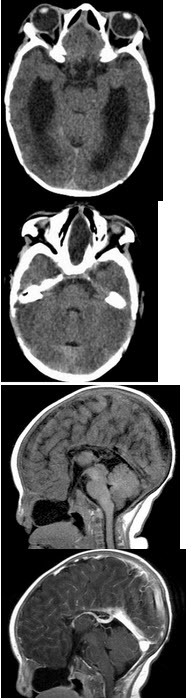

两个月女婴,口咽部有一肿块,行CT检查如图,请选择最可能的诊断( )

A:脑积水

B:胼胝体发育不全

C:透明隔囊肿

D:前脑无裂畸形

E:Dandy-Walker综合征